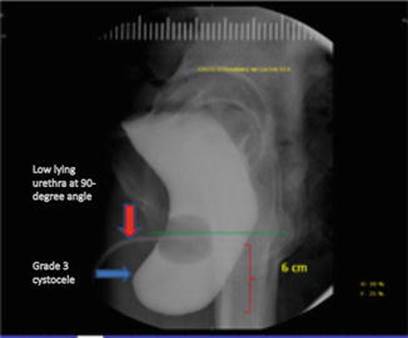

VCUG: maximum cystometric capacity (MCC) at 450 mL. Grade 3 cystocele with the lower part of the bladder at 6 cm below the lower edge of the pubic symphysis on straining views. Low-lying urethra at a 90° angle, with normal urethral views during voiding, and a moderate post-void residual confirming her clinical impression of incomplete bladder emptying (Fig. 16.1).

Fig. 16.1

Lateral view on VCUG showing a Grade 3 cystocele and a poorly supported, low-lying urethra